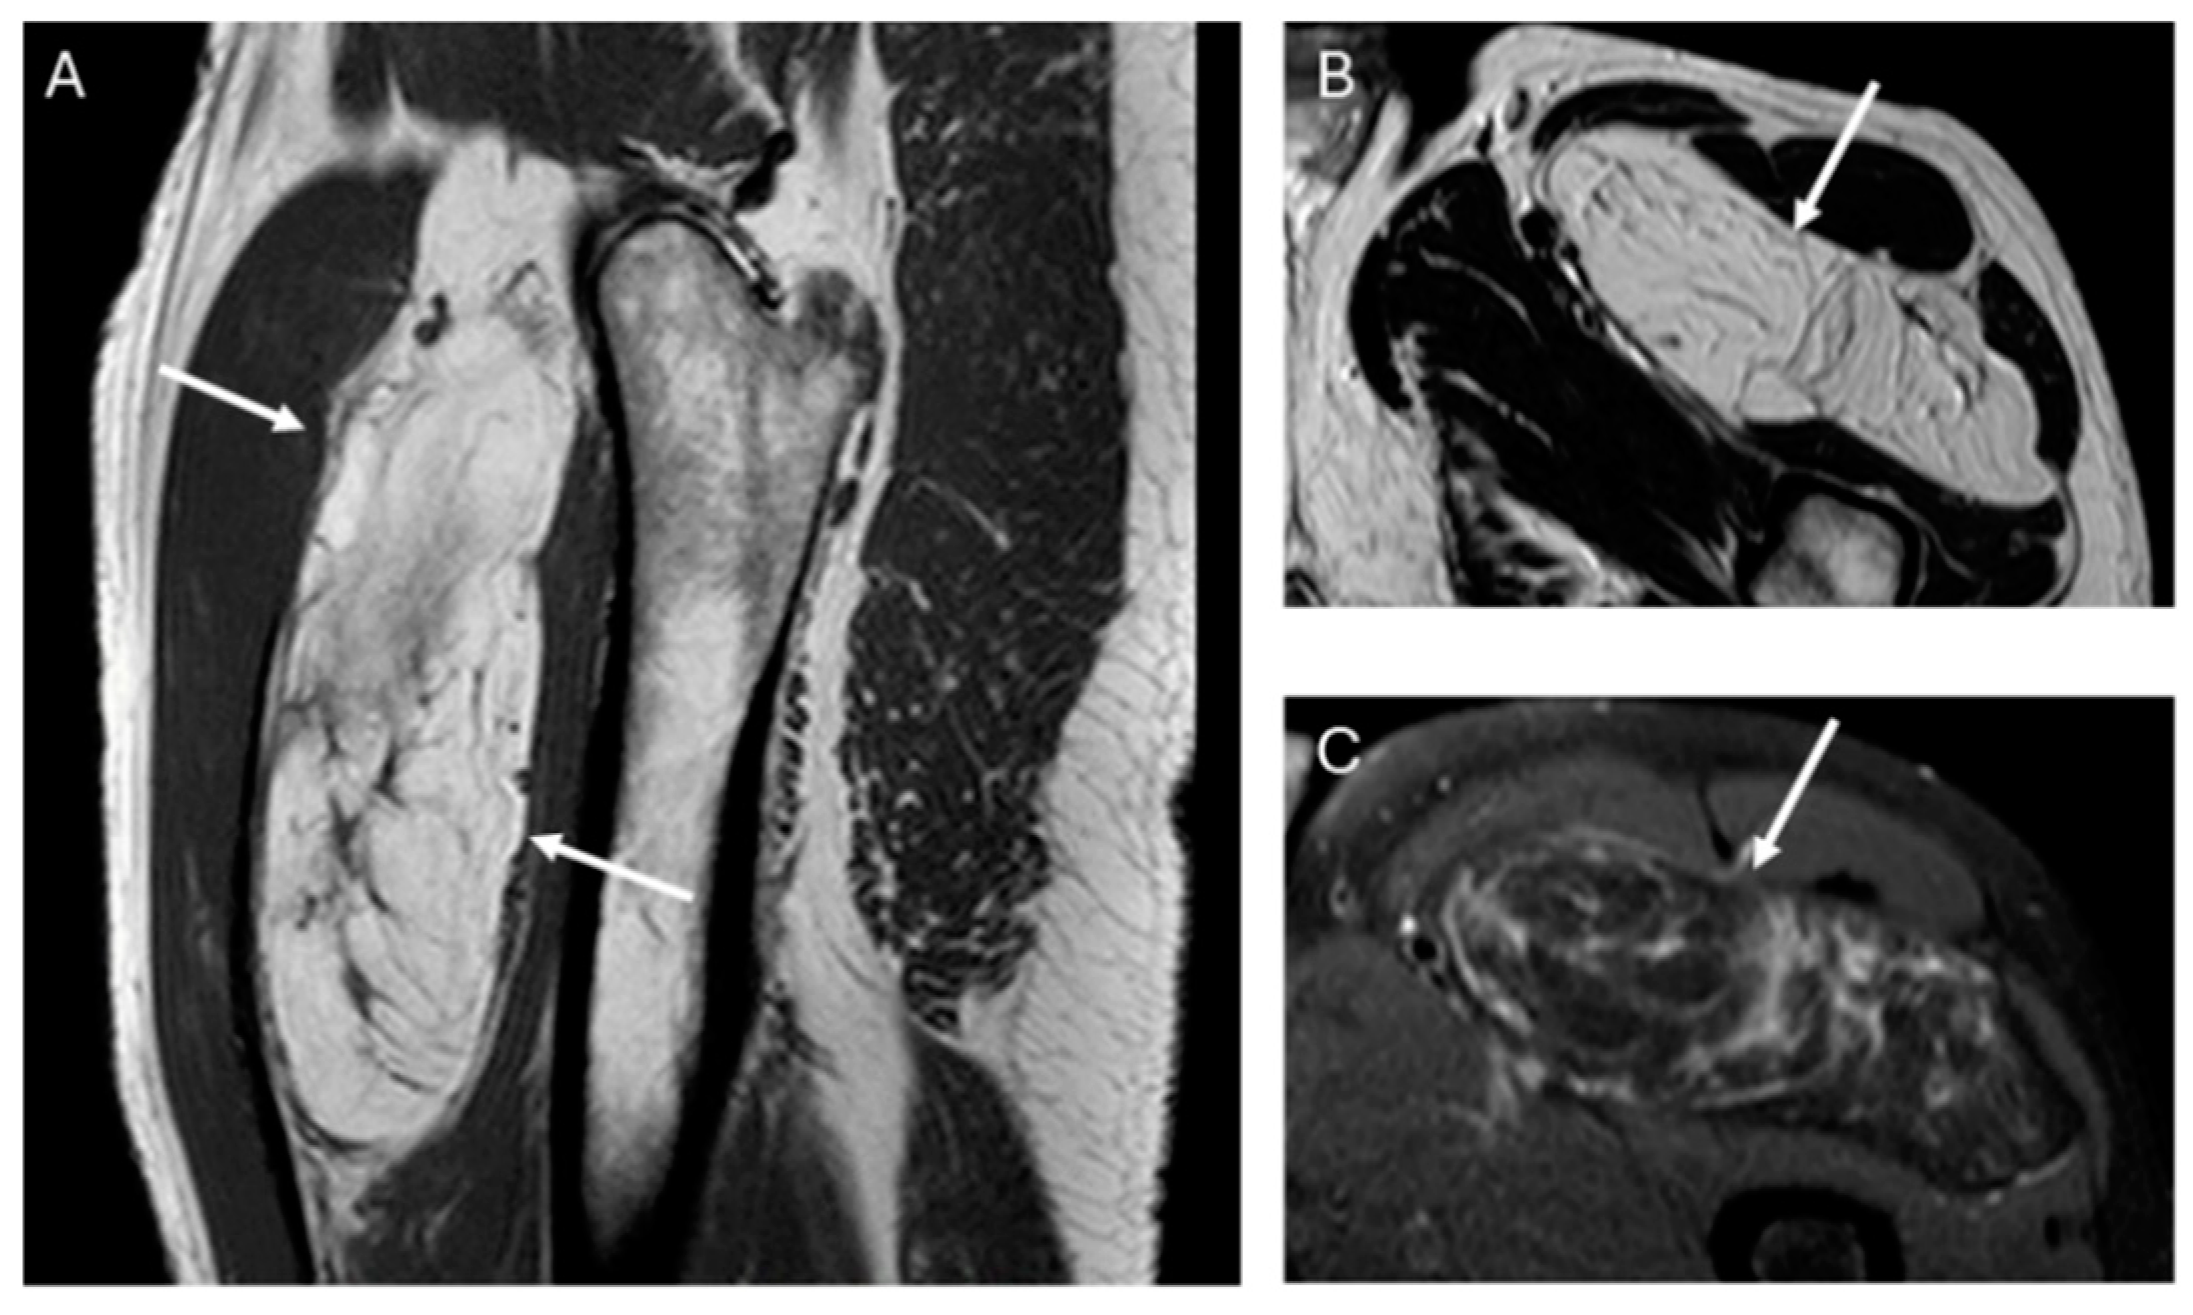

Fifty-four of the 59 lipomas had not septa or septa < 2 mm, while nineteen of 20 ALT had septa and these were ≥2 mm in 38%, (p value = 0.001) (Figure 2).

Figure 2.

Sagittal T1W (A) and axial T2W (B) and DP SPAIR (C) MR images with a heterogeneous lipomatous mass (arrows) in the anterior compartment of the left thigh. The final diagnosis was atypical lipomatous tumor (ALT) confirmed as MDM2 positive.

The presence and thickness of septa show significant differences between lipomas and ALTs. This one agrees with the findings of Kransdorf and Hosono, where the septa were thick and irregular in ALT/WDL and thin in lipoma [12,16]. Similarly, Brisson observed that lipomas were isointense to subcutaneous fat and may contain a few thin septa [17]. In our series, the absence of septa indicates lipoma and septa ≥ 2 mm is suggested of ALT. Septa < 2 mm can be indicative of either lipoma or ALTs (Figure 5).